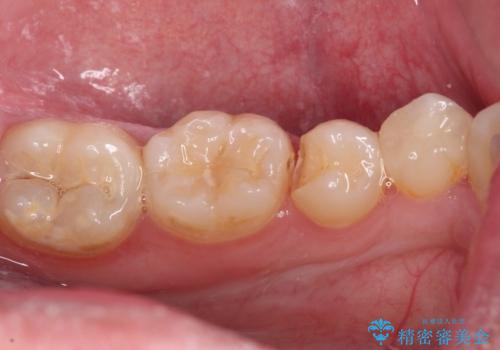

詰め物が欠けた セラミックインレーによる修復

- 以前治療した詰め物が欠けてしまったことを主訴として来院した患者様です。

食べ物がはさまったり、冷たいものがしみるといった症状がみられました。

むし歯の染め出し液と拡大鏡を用いて、むし歯がないことを確認し、

セラミックインレーにて修復することとしました。

食べ物がはさまりにくくなり、冷たいものがしみる症状もなくなり、大変満足していただきました。